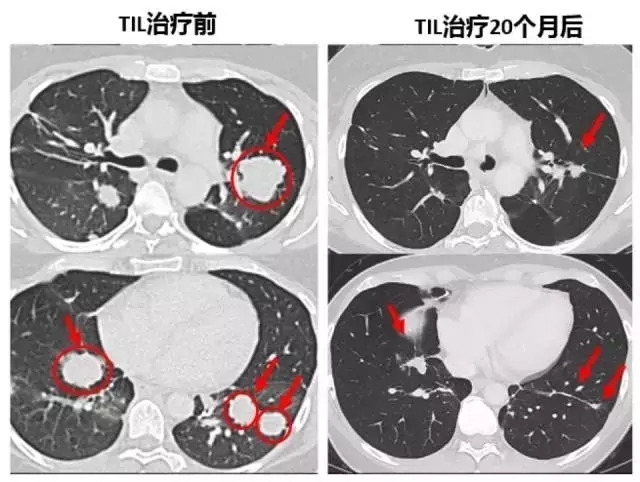

下面的對照圖可以非常明顯看到,第二次治療前肺部布滿的腫瘤,包括一些個頭非常大的,第二次TIL治療20個月后復查,這些腫瘤都非常顯著的縮小了,現在她已經成為了十年幸存者!